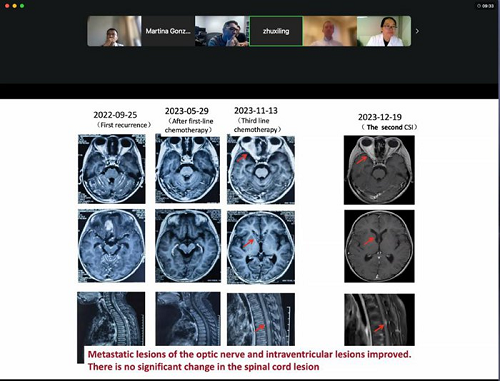

会议围绕2例复发儿童髓母细胞瘤病例的治疗过程进行讨论。针对右安门医院申戈主任团队汇报的对于难治性复发髓母细胞瘤进行再放疗的病例,UAB儿童医院放疗科的吉里什·达尔(Girish Dhall)教授结合美国的临床经验,为大家分享了自己对于类似病例的治疗经验。他表示,术后整合诊断是决定放、化疗方案的关键,尤其是在儿童肿瘤的治疗中,应严格控制放疗剂量,以减少对生长发育的影响。此外,他还着重强调二次放疗后的长期随访,并且警惕继发肿瘤的可能性。